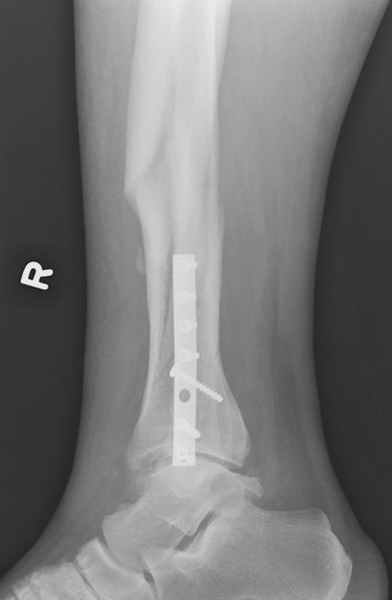

У меня молодой врач на линии, снимки отправил через эл. почту,

спрашивает что делать с больным который поступил недавно, фермер 55 лет падение при пьяной драке в баре, года два назад перенес операцию на лодыжке, на снимках и КТ перелом без вовлечения сустава,

Здесь мы использовали новый Synthes Nail с дополнительными дырками, в проксимальной части 4: по две косых и поперечные (один стандартный а другой динамический), в дистальной части две поперечные, прямая и косая. Вес больного более 120 кг, нагрузку начнем через месяц.

Получилось красиво, поздравляю. Вверху можно было ограничиться одним винтом во фронтальное статическое отверстие, зачем два 45-градусных?

При такий спирали задний край tibia может быть сломан - нет ли этого в данном случае? На всякий случай можно было ввести 1-2 винта 4,5 мм спереди назад мимо гвоздя. Хотя самый дистальный блокирующий винт, возможно, зацепил этот отломок. А какой тут диаметр гвоздя и locking винтов?